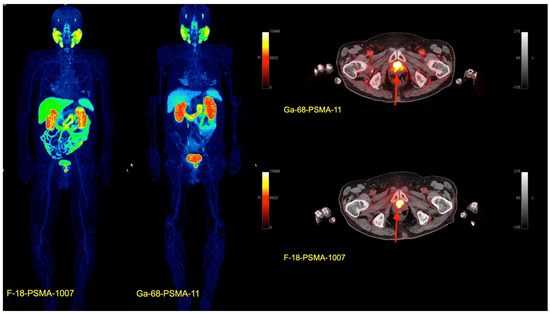

- Afshar-Oromieh, A.; Avtzi, E.; Giesel, F.L.; Holland-Letz, T.; Linhart, H.G.; Eder, M.; Eisenhut, M.; Boxler, A.; Hadaschik, B.A.; Kratochwil, C.; et al. The diagnostic value of PET/CT imaging with the 68Ga-labelled PSMA ligand HBED-CC in the diagnosis of recurrent prostate cancer. Eur. J. Nucl. Med. Mol. Imaging 2015, 42, 197–209. [Google Scholar] [CrossRef]

- Giesel, F.L.; Knorr, K.; Spohn, F.; Will, L.; Maurer, T.; Flechsig, P.; Neels, O.; Schiller, K.; Amarai, H.; Weber, W.A.; et al. Detection Efficacy of 18F-PSMA-1007 PET/CT in 251 Patients with Biochemical Recurrence of Prostate Cancer After Radical Prostatectomy. J. Nucl. Med. 2019, 60, 362–368. [Google Scholar] [CrossRef]

- Sartor, O.; de Bono, J.; Chi, K.N.; Fizazi, K.; Herrmann, K.; Rahbar, K.; Tagawa, S.T.; Nordquist, L.T.; Vaishampayan, N.; El-Haddad, G.; et al. VISION Investigators. Lutetium-177-PSMA-617 for Metastatic Castration-Resistant Prostate Cancer. N. Engl. J. Med. 2021, 385, 1091–1103. [Google Scholar] [CrossRef]

- Capasso, G.; Stefanucci, A.; Tolomeo, A. A systematic review on the current status of PSMA-targeted imaging and radioligand therapy. Eur. J. Med. Chem. 2024, 263, 115966. [Google Scholar] [CrossRef] [PubMed]